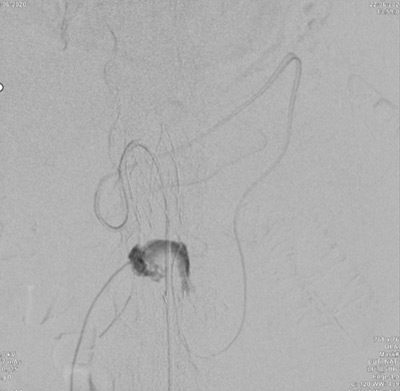

Transcaval embolisation (TCE)

- Transcaval access

- Embolisation of the sac and afferents